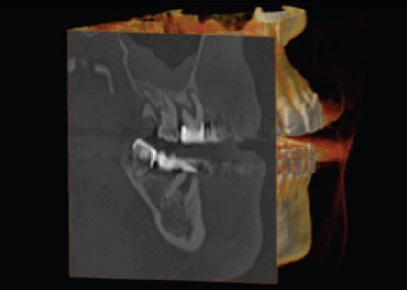

Так, на рис. 1 представлена компьютерная томограмма челюстей, зубы 46 и 48 необходимо удалить по поводу обострения хронического периодонтита и невозможности эффективного повторного эндодонтического лечения.

Рис. 1. Хронический периодонтит зубов 46 и 48. Инфицированный периодонт может стать причиной развития альвео лита в п остэкстракционном периоде.

Рис. 1. Хронический периодонтит зубов 46 и 48. Инфицированный периодонт может стать причиной развития альвеолита в постэкстракционном периоде.